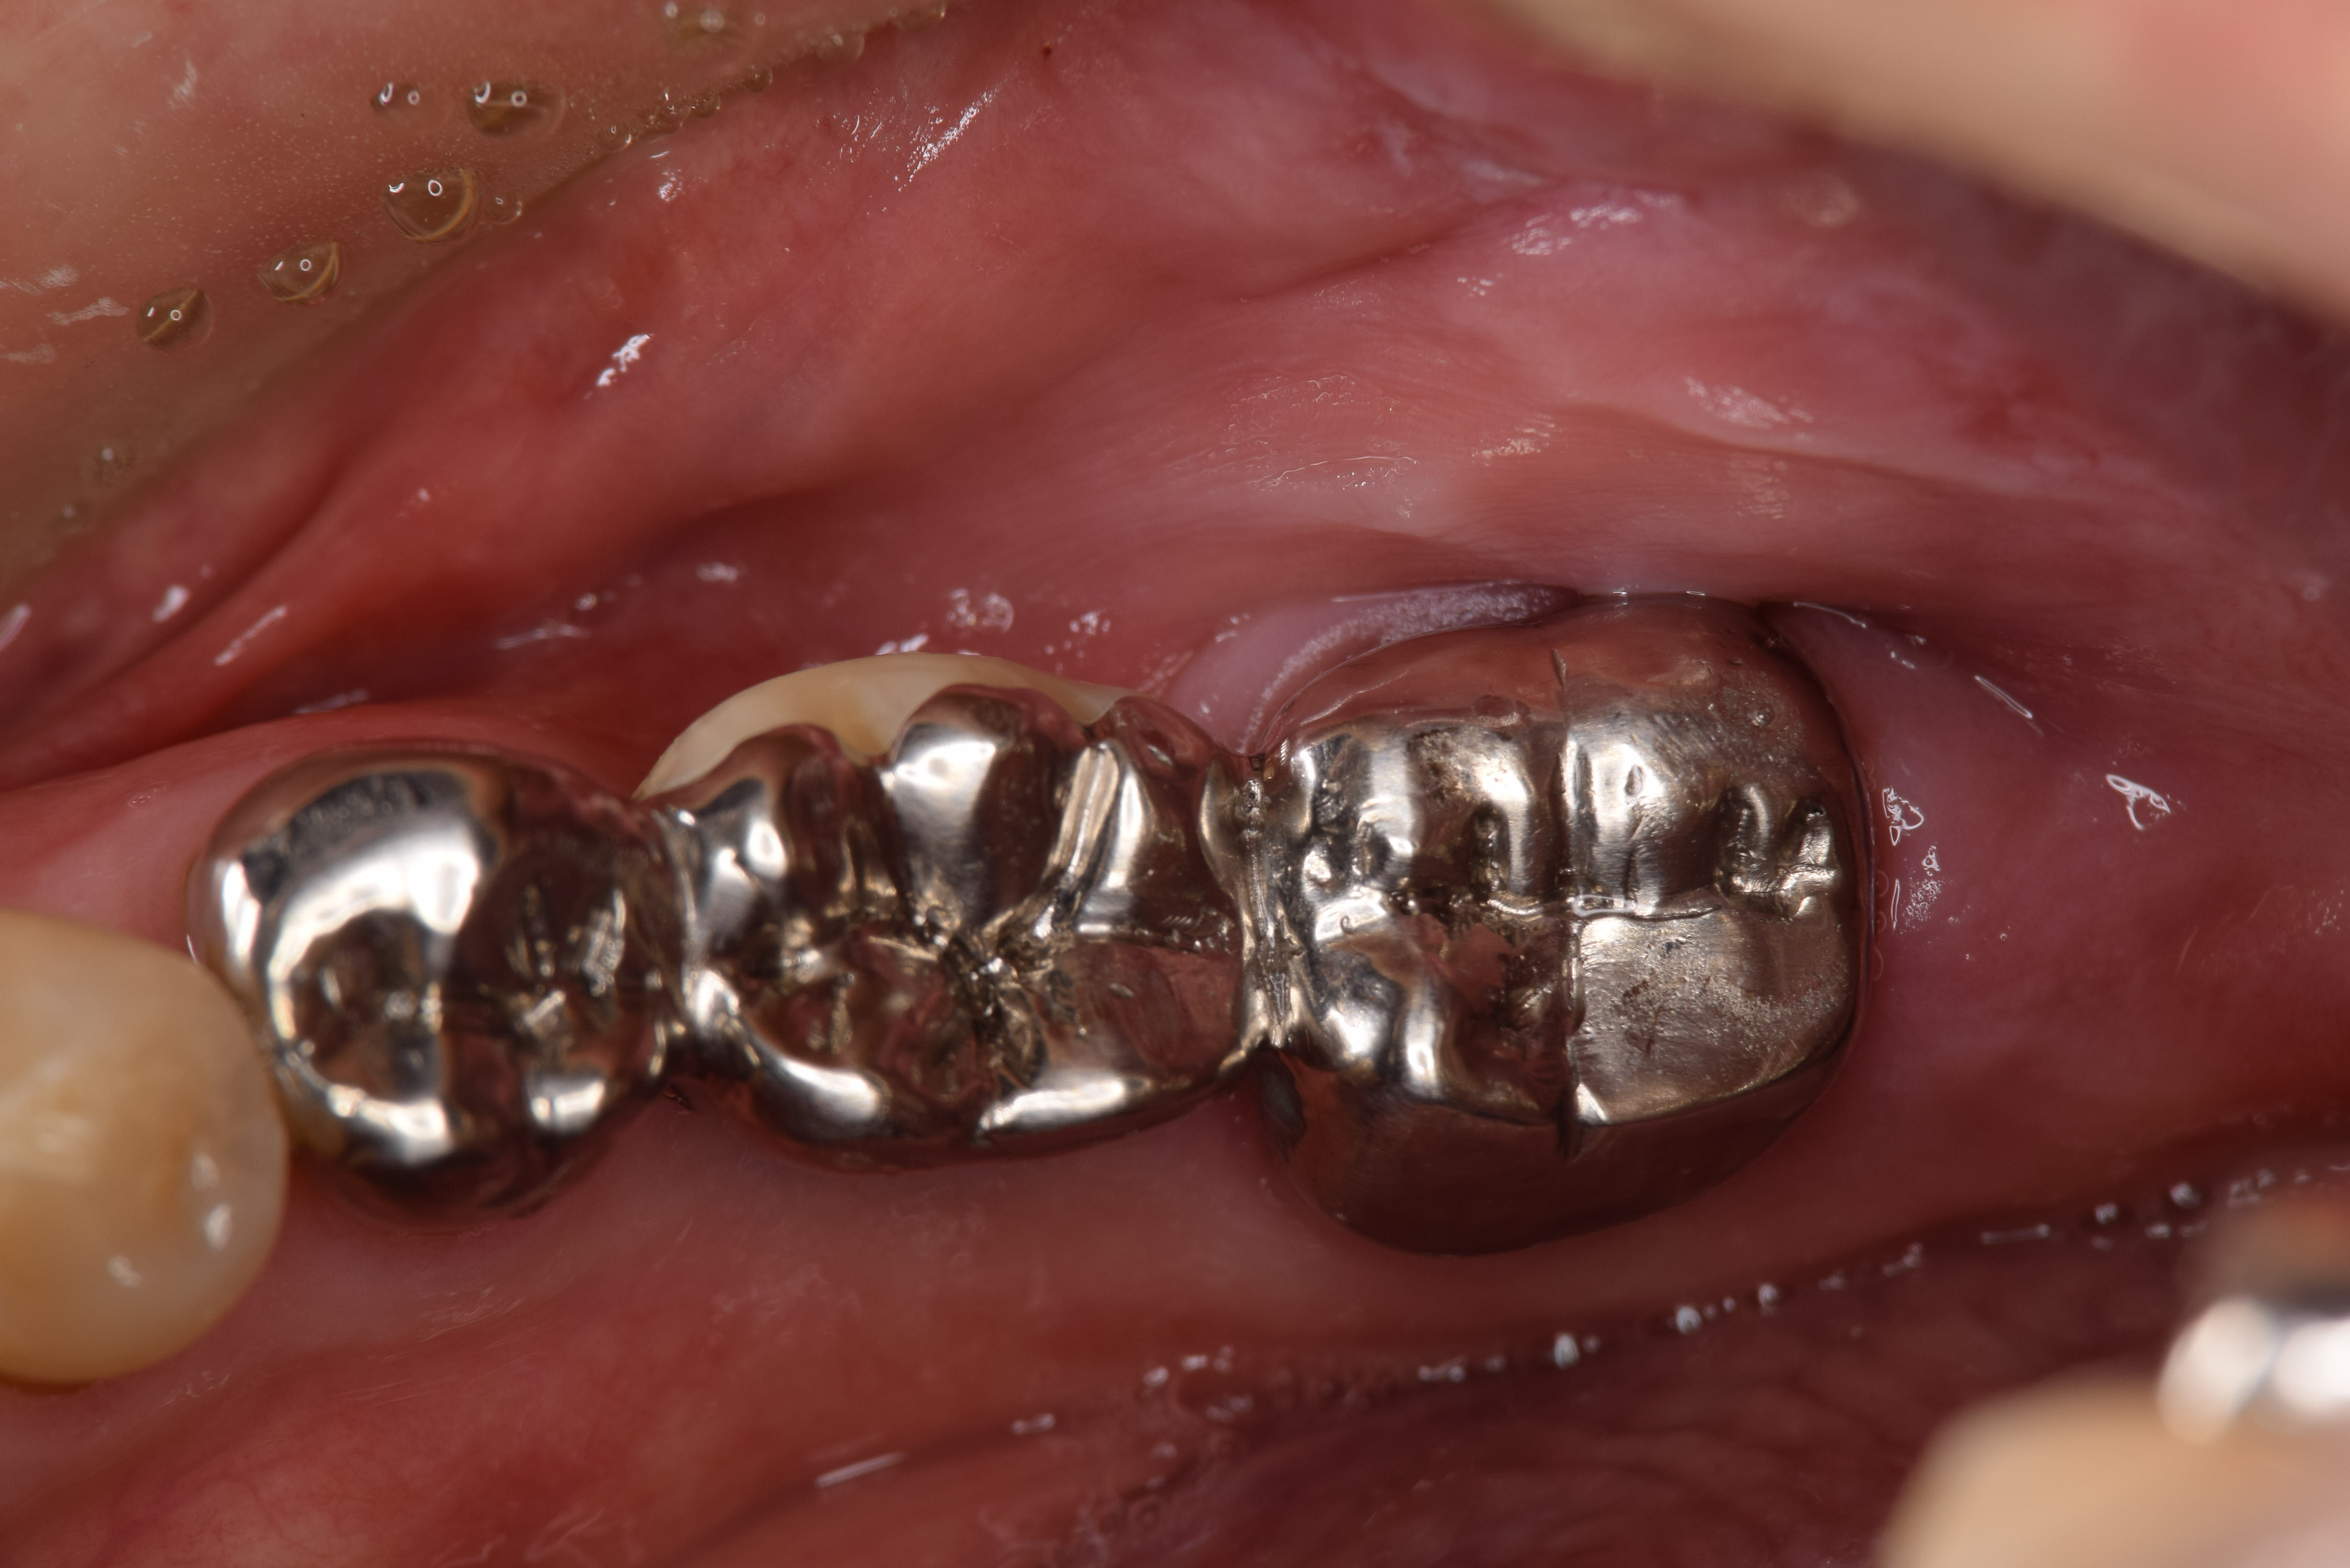

今回のケースでは左下7番が悪くなっていました(写真はミラー像)

綺麗にした歯牙を再度骨の中へ再植していきます。(写真はミラー像)

この歯を失ってしまうと義歯またはインプラントになってしまうためその二つを避けることができました。(写真はミラー像)